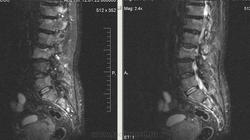

Метастазы рака простаты, кроме измений в позвонках видна сама первичная опухоль и лимфатические узлы (общий и наружный подвздошные слева, ещё один в левой подвздошной ямке).

После добавления томограмм исследования органов малого таза картина стала ещё печальнее...

Да, запустил пациент. До этого были проблемы с мочеиспусканием, рези, болезненность. Лечился самостоятельно от простатита, отмечал временное улучшение.